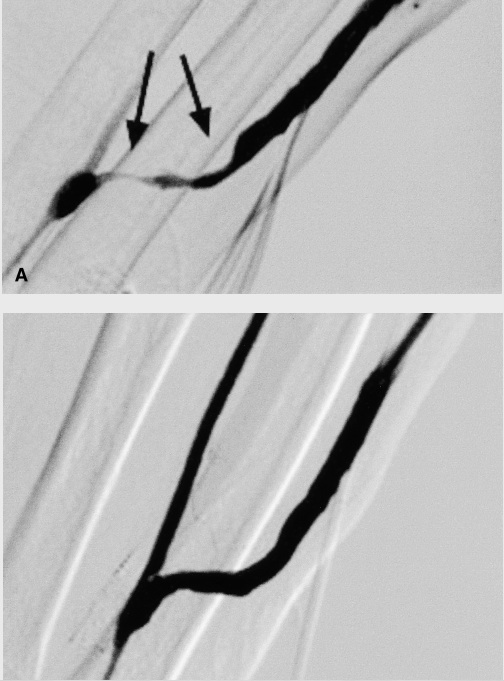

As you can see, an adequate evaluation with dopplers can usually ensure no pre-existing vascular conditions exist, leaving the 2 most common causes of early AVF failure as the presence of accessory branches and juxta-anastomotic stenosis. Early recognition is essential, since vascular interventions can save the fistula on both the above occasions.

3. Hi Yudi, dopplers are used before fistula placement in the evaluation of the vessels size. Once you have a fistula that is not maturing, fistulogram is the gold standard since it can be both diagnostic and therapeutic. I do believe angioplasty can help maturation in some cases, but I still think outcomes are less than optimal.

Any comments on using ballon assisted maturation of fistulas? Something I'm trying at the moment